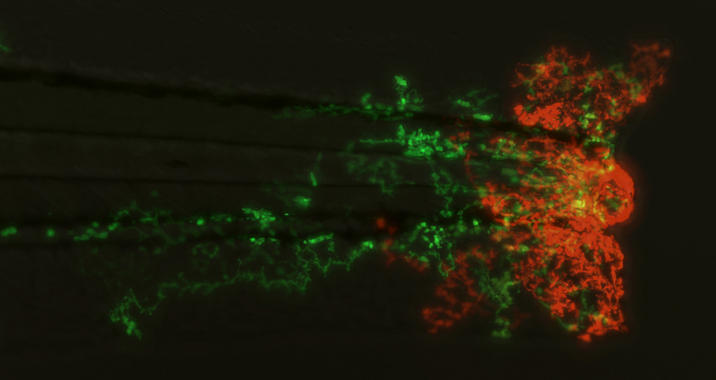

Proyección de los neutrófilos en un pez cebra. Imagen: A.L. Robertson. Fuente: Universidad de Sheffield/Sinc.

Gracias al cribado de fármacos en ensayos con peces cebra, los investigadores encontraron un compuesto de la salvia roja, Tanshinona IIA, que redujo la inflamación al eliminar los neutrófilos haciéndolos ‘morir’ en la herida y moviéndolos fuera de ella –una forma completamente nueva de tratar la inflamación–.

Para llevar a cabo el estudio, los investigadores modificaron un modelo de pez cebra (genéticamente etiquetado con proteína verde fluorescente) en el que los neutrófilos brillaban. “Las larvas de pez cebra son un modelo ideal para la detección de fármacos en animales vivos debido a su pequeño tamaño, su transparencia óptica y la facilidad de manipulación genética y farmacológica”, señala a Sinc Stephen Renshaw, del departamento de Infección e Inmunidad de la institución inglesa y uno de los autores principales del estudio

Gracias al cribado de fármacos en ensayos con peces cebra, los investigadores encontraron un compuesto de la salvia roja, Tanshinona IIA, que redujo la inflamación al eliminar los neutrófilos haciéndolos ‘morir’ en la herida y moviéndolos fuera de ella –una forma completamente nueva de tratar la inflamación–.

Para llevar a cabo el estudio, los investigadores modificaron un modelo de pez cebra (genéticamente etiquetado con proteína verde fluorescente) en el que los neutrófilos brillaban. “Las larvas de pez cebra son un modelo ideal para la detección de fármacos en animales vivos debido a su pequeño tamaño, su transparencia óptica y la facilidad de manipulación genética y farmacológica”, señala a Sinc Stephen Renshaw, del departamento de Infección e Inmunidad de la institución inglesa y uno de los autores principales del estudio